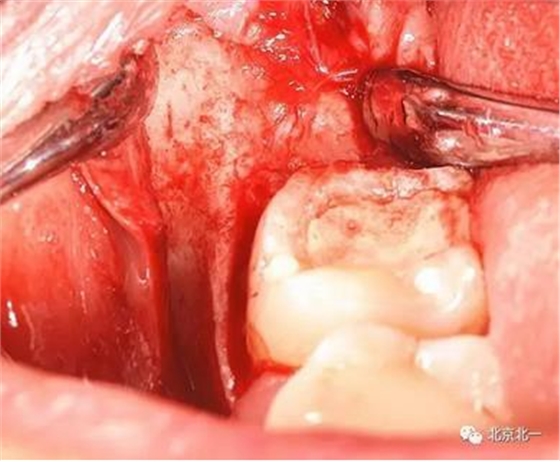

圖六:切開翻瓣, 看見骨面清晰,未見智齒

圖七:去骨后看不見牙齒位置方向。顏色無法區(qū)分,拍片確認一下剛才去骨的以及截的冠就是智齒。